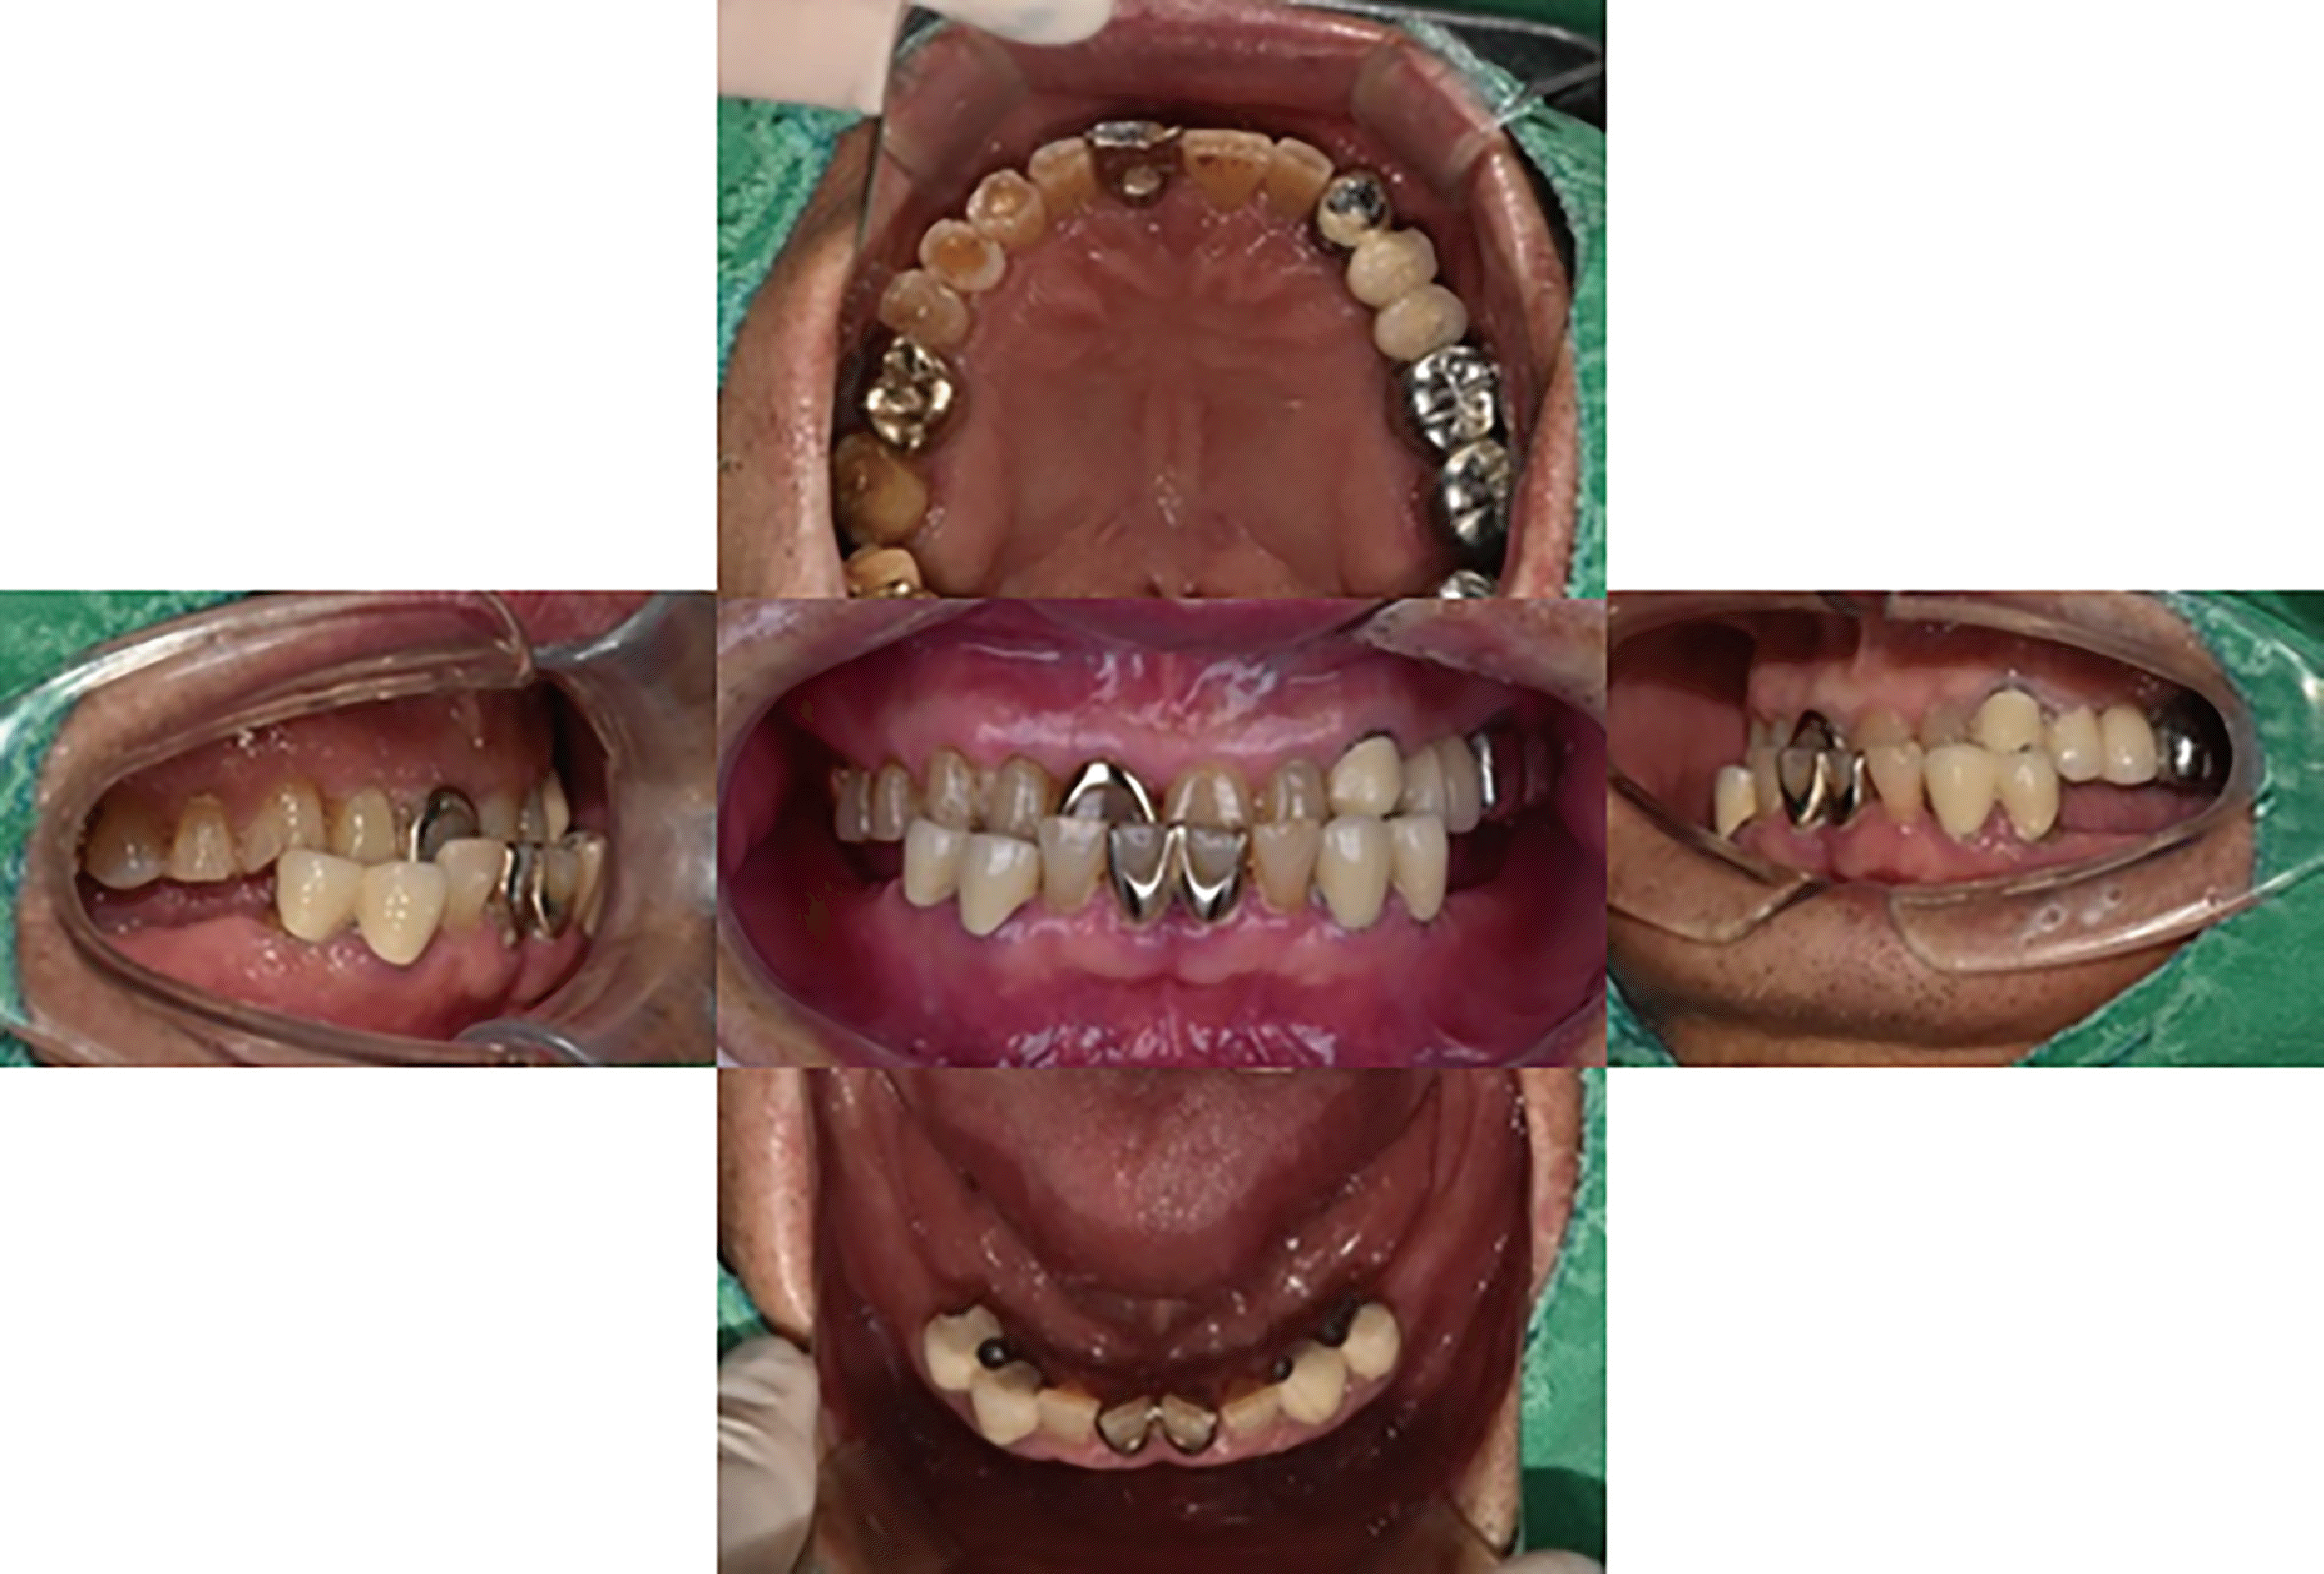

Fig. 8

(A) The panorama image of the final treatment, (B) The intraoral image and facial profile after final treatment.

Provisional Highness® restorations and base abutments on #34-37 were removed, and compatible scan bodies were attached for maxillary, mandibular, and buccal bite scans using the stable right and anterior bite registration. One week later, custom abutments and zirconia prostheses for #34-37 were delivered (Fig. 5). Following final restoration of the left mandibular posterior region, provisional restorations and base abutments on #43, 45-47, along with maxillary anterior provisionals, were removed. Final preparations were completed on #11-13, 21, and 22, and scan bodies were placed on #43, 45-47. Scans were obtained using the stable left-side bite registration (Fig. 6). One week later, zirconia crowns for #11, 12, 13, 21, and 22, custom abutments for #43, 45-47, and zirconia prostheses for #43-45 and #46-47 were delivered. Partial group function occlusion was maintained during lateral excursions (Fig. 7, 8). At six months post-treatment, the patient reported no functional discomfort, and radiographic evaluation, including panoramic and cephalometric images, confirmed stable occlusion and TMJ position in proper centric relation (Fig. 9).